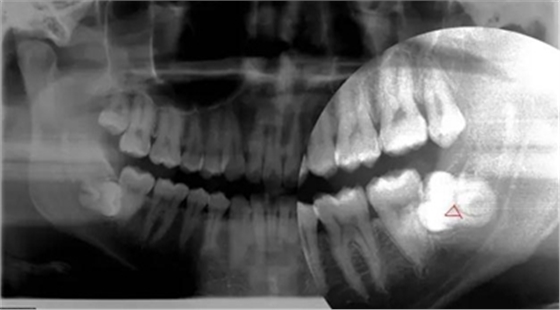

熟悉牙體牙周解剖形態(tài),設(shè)計拔牙手術(shù)方案,評估牙齒脫位道及周圍軟硬阻力,控制用力大小和方向,避免周圍組織以及對合牙齒的損傷,考慮如何用最小的力,最小的拔牙創(chuàng)傷,最短的時間拔除患牙。拔牙時先將牙齒進行分割后使用微創(chuàng)拔牙器

械,輕輕地插入需要拔除的牙齒周圍,切斷相互連接的牙周韌帶,使牙齒充分松動并輕松脫出。微創(chuàng)拔牙要求無痛局部麻醉,追求零敲擊、小創(chuàng)傷理念,利用各種微創(chuàng)器械,對術(shù)區(qū)組織進行嚴格的保護,達到創(chuàng)傷最小化。患者拔牙時更加舒適,使拔

智齒水平阻生(長橫過來了),影響前面牙齒或者致前面牙齒擁擠不齊

1.水平阻生影響前牙